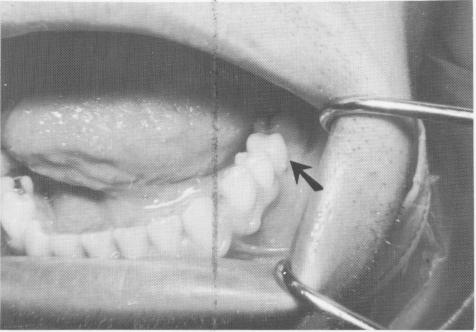

Fig. 8-5. The implant post should extend 3 or 4 mm. above the fibromucosal tissue and should not interfere with occlusion.

Fig. 8-4. With the use of a hand ratchet and a prolongator, the vent-plant is self-tapped into the underlying osseous structures.